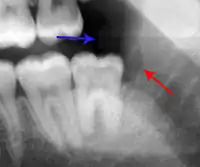

The periodontal ligament becomes inflamed and there may be pain when biting or tapping on the tooth. On an X-ray, bone resorption appears as a radiolucent area around the end of the root, although this does not manifest immediately.[10]: 228 Acute apical periodontitis is characterized by well-localized, spontaneous, persistent, moderate to severe pain.[6]: 125–135 The alveolar process may be tender to palpation over the roots. The tooth may be raised in the socket and feel more prominent than the adjacent teeth.[6]: 125–135

Decay (green) with apical abscess (blue)

Gutta-percha point indicating abscess origin